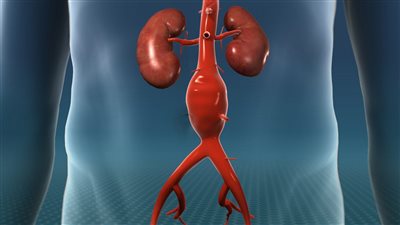

- أو قد تتضرر بعض الأعضاء ويصاب الشخص بالفشل الكلوي أو تحدث أضرار معوية تهدد حياته.

ولمن يرغب في معرفة إجاية سؤال ما هو إنسلاخ الشريان الأورطي؟، يوضح أخصائي أمراص الباطنة والقلب والصدر، أن انسلاخ الشريان الأورطى يعد من الحالات الطبية الخطيرة والتي تصيب الطبقات الداخلية للشريان؛ حيث تنسلخ تنفصل الطبقة الداخلية عن الطبقة الوسطى للشريان؛ نتجو تراكم الدم بينهما، منبهًا إلى قد يسبب الوفاة في حال انفجر الشريان.

جدير بالذكر أن تسلخ الأورطي عد من الحالات الشائعة لدى الرجال أكثر من غيرهم وخاصة كبار السن.

- أو يمكن تناول الأدوية المثبطة للنبض وضغط الدم، لاسيما في حال المعاناة من التسلخ من النوع ب غير الخطر والذي لا يؤثر على تدفق الدم إلى أعضاء هامة كالشرايين الكلوية.